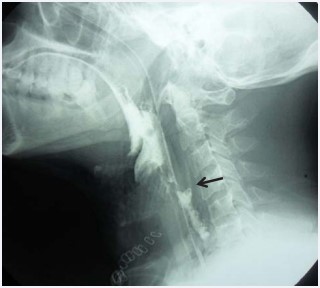

The current study that was held in Ain Shams University hospitals in 2013 and 2014discussedthe use of autologous fascia lata graft (AFLG) aided with pedicled muscle flap in the repair of pharyngeal tears. This study included four patients; three adult male patients presented to the emergency room with history of gunshot in the neck, neck swelling, stridor, absolute dysphagia, hematemesis, and shock. They were subjected to ant shock measures, nasogastric tube (NGT) insertion, CT scan neck without contrast (Figure 1),

gastrographin swallow (Figure 2)

Figure 2: Gastrographin swallow. Showing loss of cervical lordosis denoting neck muscles spasm, widening of the prevertebral space due to edema and surgical emphysema. Ba leak into the retropharyngeal space (arrow) is noted at the level of upper border of C4.